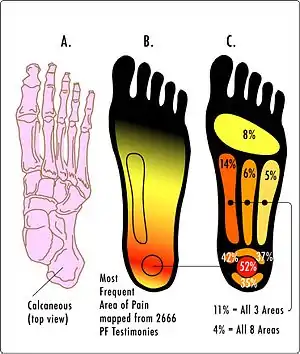

| Most common areas of pain in plantar fasciitis | |

Plantar fasciitis is a disorder of the connective tissue which supports the arch of the foot.[2] It results in pain in the heel and bottom of the foot that is usually most severe with the first steps of the day or following a period of rest.[2][4] Pain is also frequently brought on by bending the foot and toes up towards the shin.[3][4] The pain typically comes on gradually, and it affects both feet in about one-third of cases.[2][3]

When plantar fasciitis occurs, the pain is typically sharp[10] and usually unilateral (70% of cases).[7] Bearing weight on the heel after long periods of rest worsens heel pain in affected individuals.[11] Individuals with plantar fasciitis often report their symptoms are most intense during their first steps after getting out of bed or after prolonged periods of sitting.[4] Symptoms typically improve with continued walking.[4][6][10] Rare, but reported symptoms include numbness, tingling, swelling, or radiating pain.[12] Typically there are no fevers or night sweats.[3]